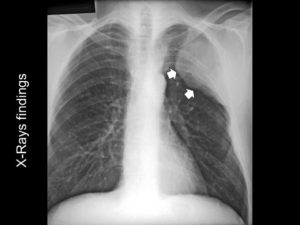

- Получение рентгеновского снимка, компьютерной и магнитно-резонансной томографии — на них явно видно расширение бронхов и усиление их рисунка.

При рентгенографическом обследовании можно обнаружить затемнения, локализующиеся в бронхах.

При рассмотрении рентгенографического снимка просматривается усиленный рисунок бронхиального дерева, просвет бронхов сужен, образуются бронхоэктазы.

На рентгенограммах просматривается расширение малых бронхов, явно заметно сужение их просвета, наблюдаются бронхоэктазы в большом количестве.